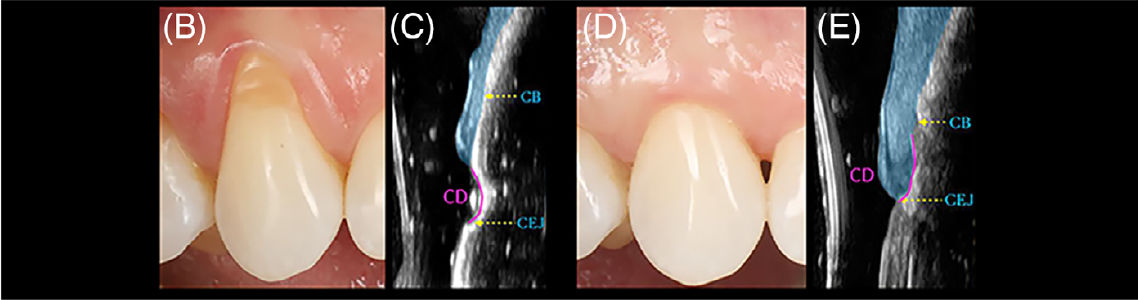

Ультразвуковая характеристика пародонтальных структур передних зубов верхней челюсти

Рис 5. (A) Ультразвуковая характеристика пародонтальных структур передних зубов верхней челюсти с комбинированными дефектами (CD), включающими рецессии десны и NCCL.Нижние панели демонстрируют ультразвуковые (US) сканы, полученные в срединно-вестибулярной области передних верхнечелюстных зубов: «CB» — альвеолярный гребень кости; «CD» — зона комбинированного дефекта (включая NCCL и рецессию); «Cr» — клиническая коронка; «R» — корень.

Мягкотканный компонент выделен синим цветом. Все участки классифицированы как A+ или B+ (Pini Prato и соавт., 2010) из-за наличия клинически определяемых ступенек, что дополнительно подтверждено высокочастотной ультразвуковой визуализацией

Типичный случай RT1 и NCCL типа A+

Рис 5. (B–E) Типичный случай RT1 и NCCL типа A+:

(A — рисунок выше) до и (B) после процедуры покрытия корня. (C) Ультразвуковое изображение на исходном этапе, отображающее альвеолярный гребень (CB), цементо-эмалевую границу (CEJ) и вогнутость комбинированного дефекта. (E) Толщина мягких тканей (синяя зона) в области CD. Данная анатомическая особенность могла способствовать поддержанию пространства и, соответственно, увеличению толщины мягких тканей